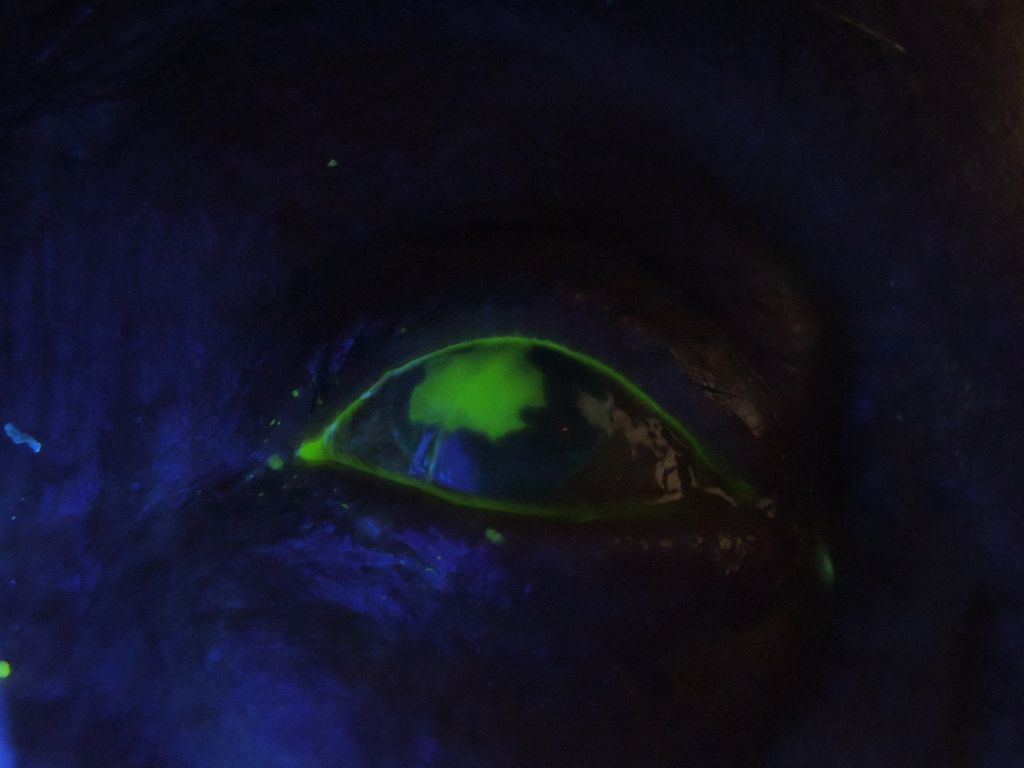

Herpes corneal. Fluoresceína y luz de Wood. Distintas fases evolutivas.